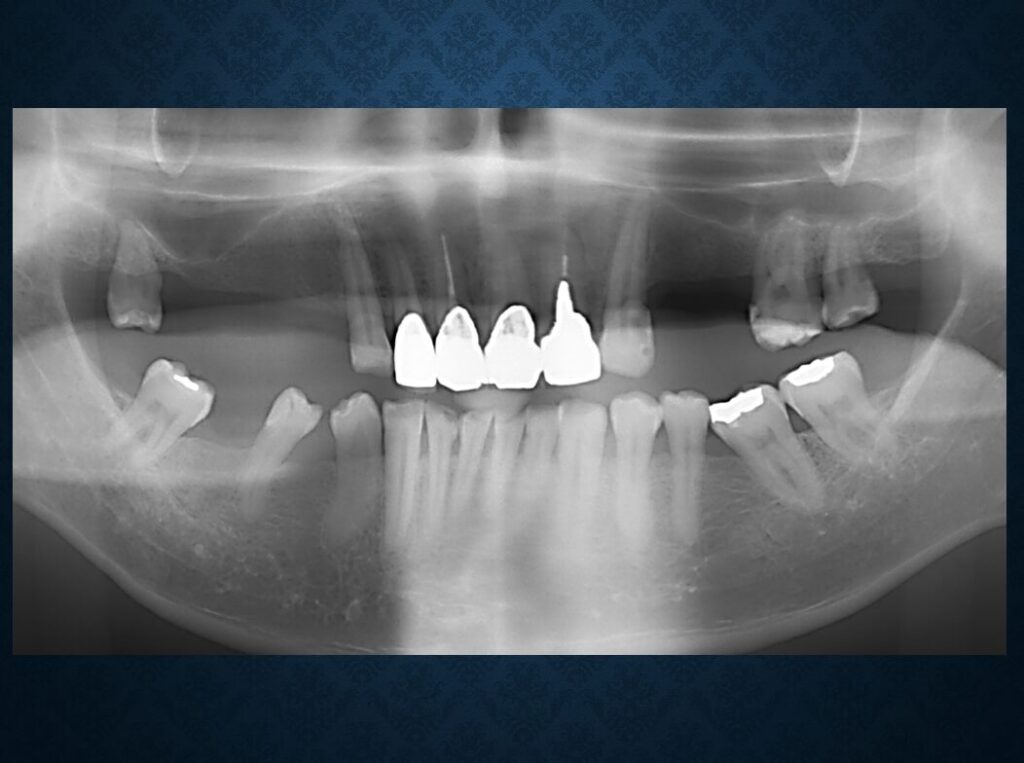

40代フィリピン人男性の方でした。欠損部には入れ歯が入っていました。インプラントに代えて欲しいというご希望でした。職業は会社経営、モデル、英会話教師、ボディービルダー、六本木警察フィリピン語講師、映画俳優など多岐にわたり、日本だけでなく、オーストラリア、台湾、スペインなどを渡り歩いている方でした。多忙を極めていらしたので治療は度々中断しましたが、無事にゴールできました。